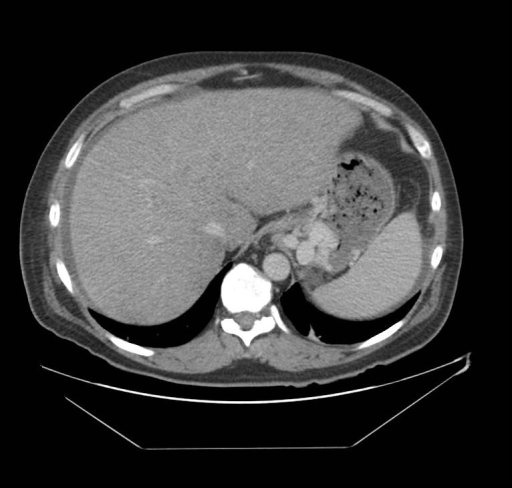

| 8 | Imaging + Clinical Features β CT image + full clinical signs list |